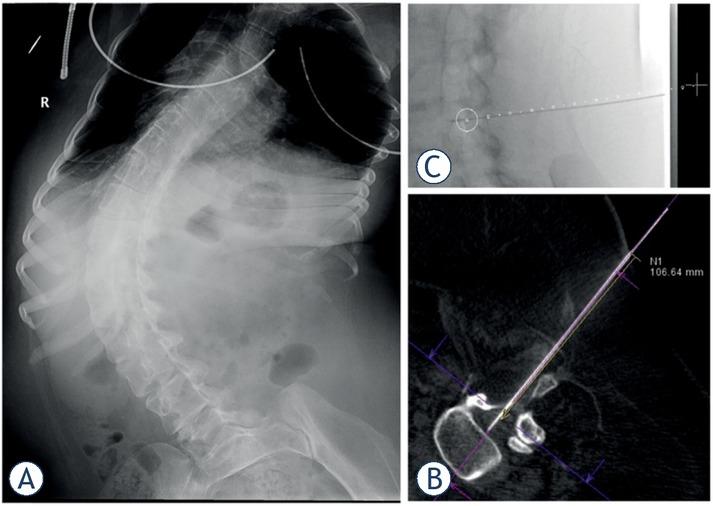

Figure 2